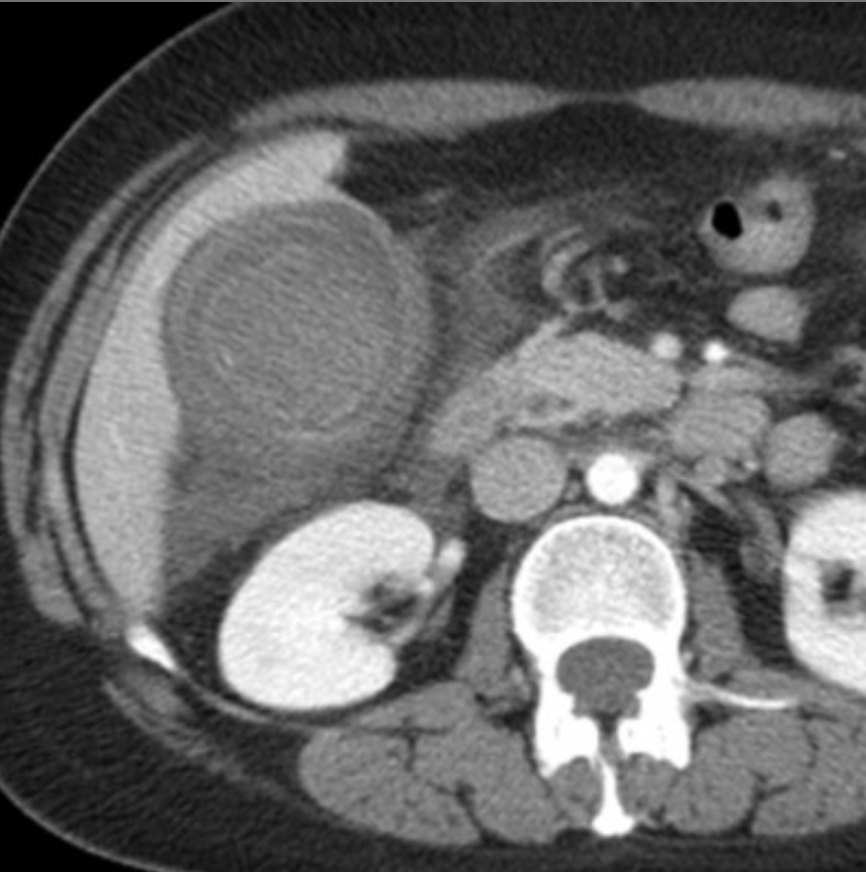

CT: hyperenhancement & thickening of bile duct walls often w/a CBD stone.